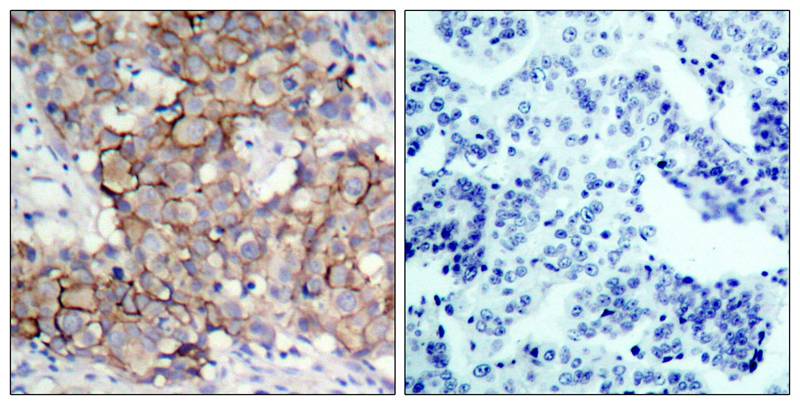

分类: 科研抗体货号: P40047别名: SLEB11应用: WB,IHC反应种属: Human,Mouse,Rat